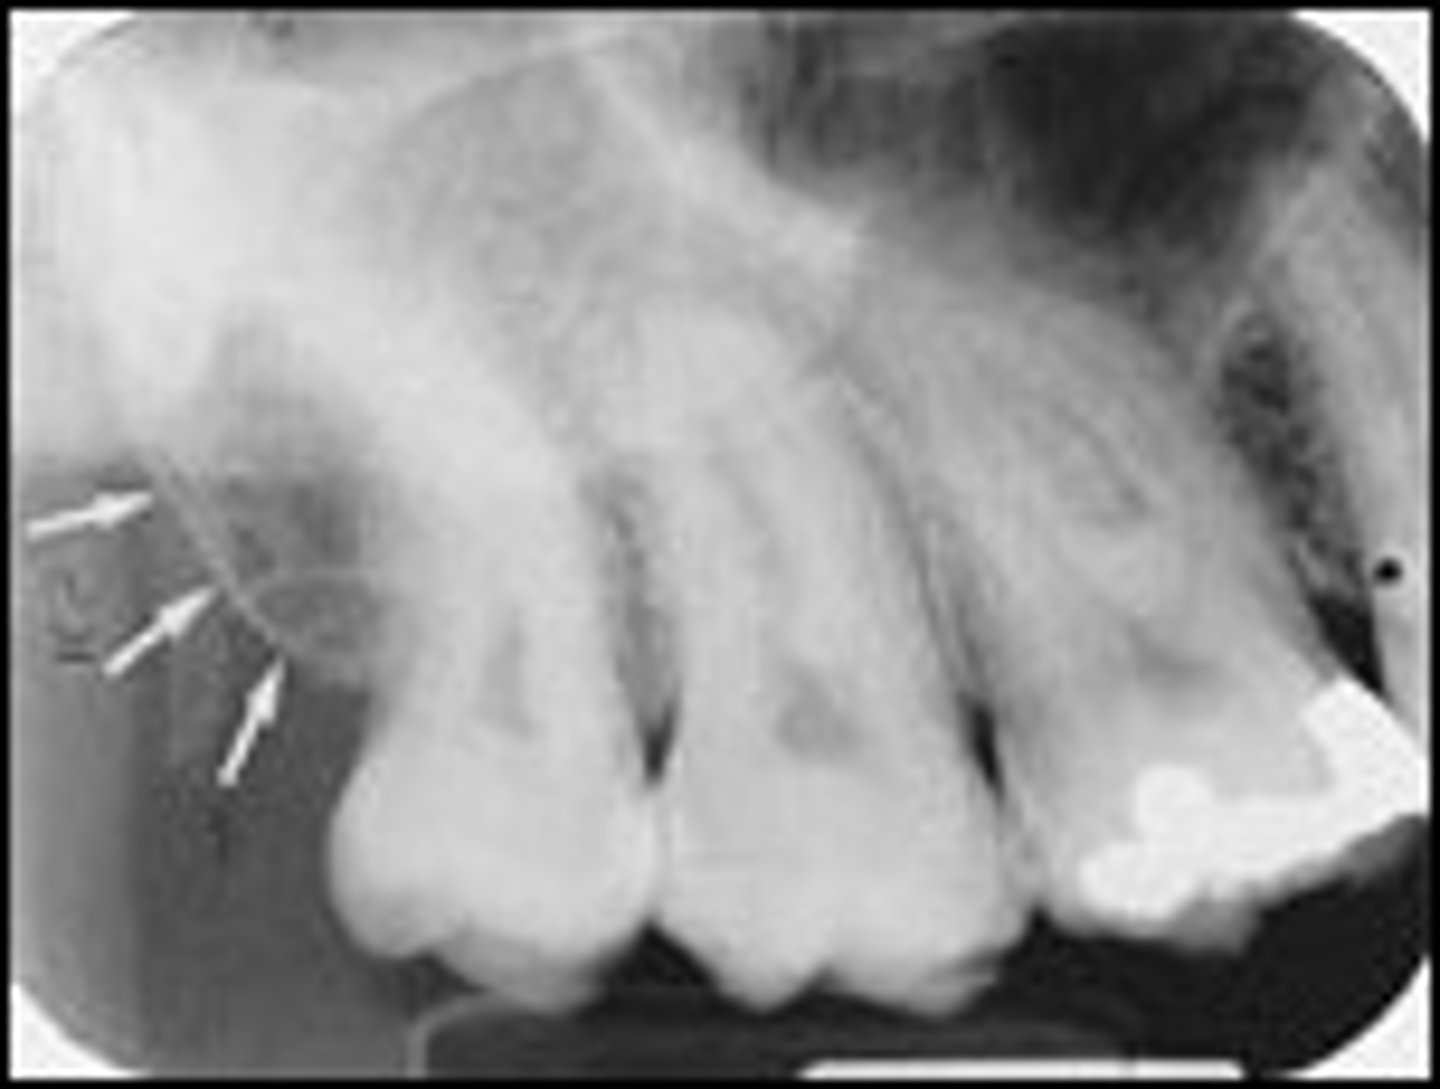

what is periodontal disease

bacterial infection of the periodontium

how does periodontal disease appear

swollen, red, bleeding gingiva with pocket formation

what does the detection of periodontal disease require

both clinical and radiographic examination

how are radiographs helpful in evaluating periodontal disease

provide an overview of the amount of bone present, and indicate the pattern and severity of bone loss

what is the best type of radiograph for detecting the periodontium

parallel PA

why does a radiograph need to be paired with a clinical examination to diagnose periodontal disease

they are two dimensional representations of three dimensional objects

what are the ways to describe bone loss

pattern, severity, and distribution

what is pattern of bone loss

described as either horizontal or vertical

what is severity of bone loss

the amound of bone lost

what is mild severity of bone loss

1-2mm bone loss

what is moderate severity of bone loss

3-4mm bone loss

what is severe severity of bone loss

5mm or more bone loss

what is distribution of bone loss

is it localized or generalized bone loss

what are predisposing factors that contribute to periodontal disease

calculus, defective restorations, malpositioned teeth, supernumerary teeth, impacted teeth, caries, fusion, gemination, dilacerations

how can malpositioned teeth affect periodontal disease

attracts more plaque, irregular contacts, thickness variations